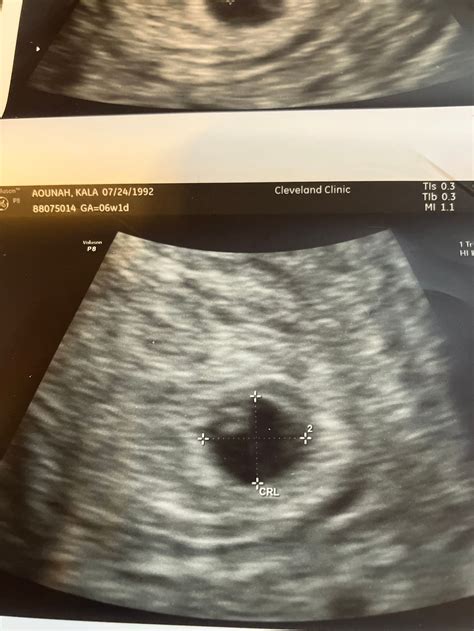

At five weeks, the embryo is still very small, measuring about 2 millimeters in length. The ultrasound will focus on detecting the gestational sac, which is a fluid-filled structure that houses the embryo. The presence of the gestational sac is a positive sign of pregnancy. Additionally, the ultrasound may reveal the yolk sac, which provides early nutrition to the embryo.

• Gestational Sac: This is the first structure that appears on the ultrasound. It looks like a small, dark circle within the uterus.

• Yolk Sac: This structure provides early nutrition to the embryo and is usually visible by the end of the fifth week.

• Embryo: At five weeks, the embryo is very small and may not be clearly visible. However, the presence of the gestational sac and yolk sac are positive indicators of a healthy pregnancy.